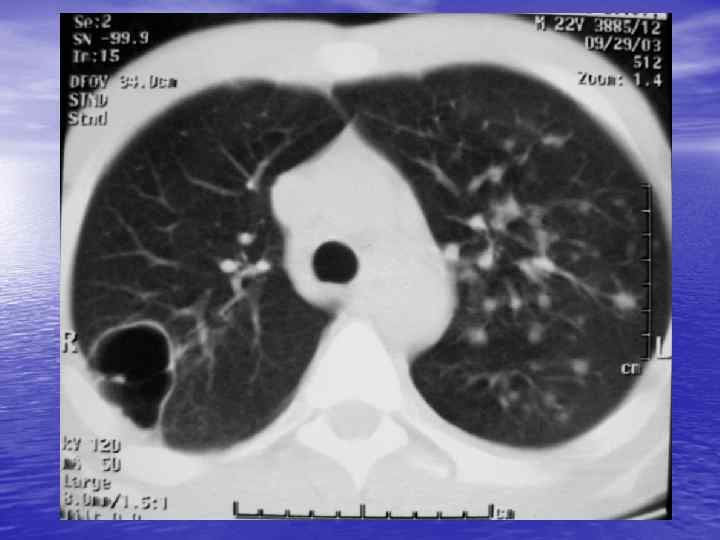

Преимущества спиральной КТ: ü Возможность проведения исследования с болюсным ü ü ü ü ü контрастированием Высокая разрешающая способность; Высокая скорость исследования; Получение высококачественных изображений костных структур; Возможность обследования всего тела; Возможность проведения исследования больных под наркозом; Возможность детальной оценки состояния крупных и периферических сосудов в условиях искусственного контрастирования; Высокая информативность метода при черепномозговых травмах в остром периоде; Ранняя диагностика ишемических и геморрагических инсультов; Метод выбора для диагностики заболеваний легких; Планирование лучевой терапии.